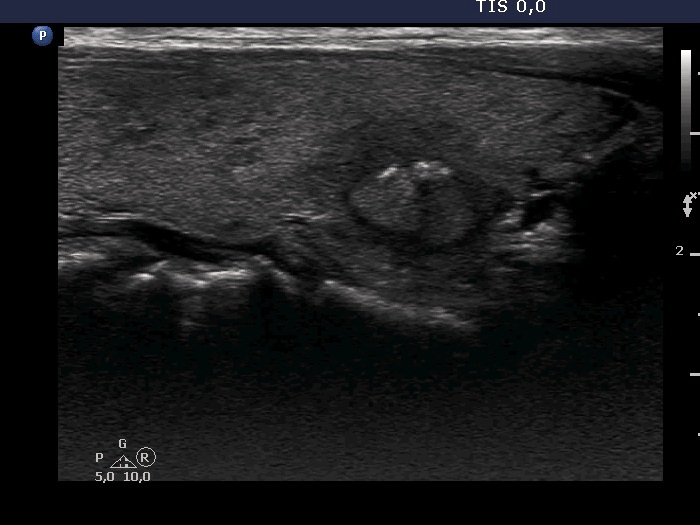

The borders of the nodule - case 2168 (ultrasonographic picture 6)

Right lobe, another longitudinal view. These figures are partly microcalcifications and based on the acoustic shadow partly macrocalcification.